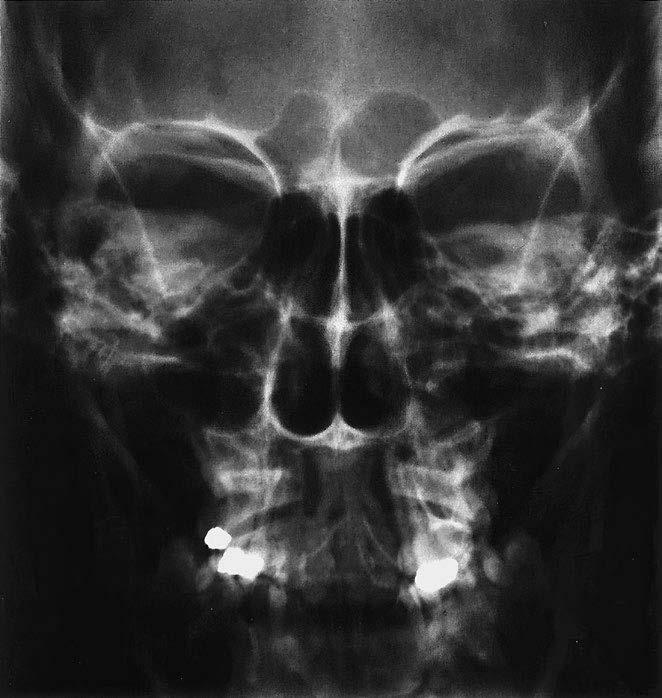

1 sutura sagittalis (šev šípový)

2 foveolae granulares

3 sutura lambdoidea (šev lambdový)

4 sinus frontalis (dutina kosti čelní)

5 strop orbity (očnice)

6 planum sphenoidale

7 cellulae ethmoidales (etmoidální sklípky / dutinky kosti čichové)

8 sutura frontozygomatica (šev mezi kostí čelní a kostí lícní)

9 horní hrana pyramidy (kosti skalní)

10 linea innominata

11 meatus acusticus internus (vnitřní zvukovod)

12 arcus zygomaticus (jařmový oblouk)

13 caput mandibulae (hlavice dolní čelisti)

14 septum nasi et concha nasalis inferior (nosní přepážka a dolní nosní skořepa)

15 sinus maxillaris (dutina horní čelisti)

16 processus mastoideus (bradavkový výběžek)

17 squama occipitalis (šupina kosti týlní)

18 dens axis (zub čepovce)

19 maxilla (horní čelist)

20 canalis mandibulae (kanál v dolní čelisti)

21 angulus mandibulae (úhel dolní čelisti)

22 mandibula (dolní čelist)

23 protuberantia mentalis (bradový výběžek)

os frontale (kost čelní)

os occipitale (kost týlní)

os temporale (kost spánková)

os zygomaticum (kost lícní)

os parietale (kost temenní)

os sphenoidale (kost klínová)